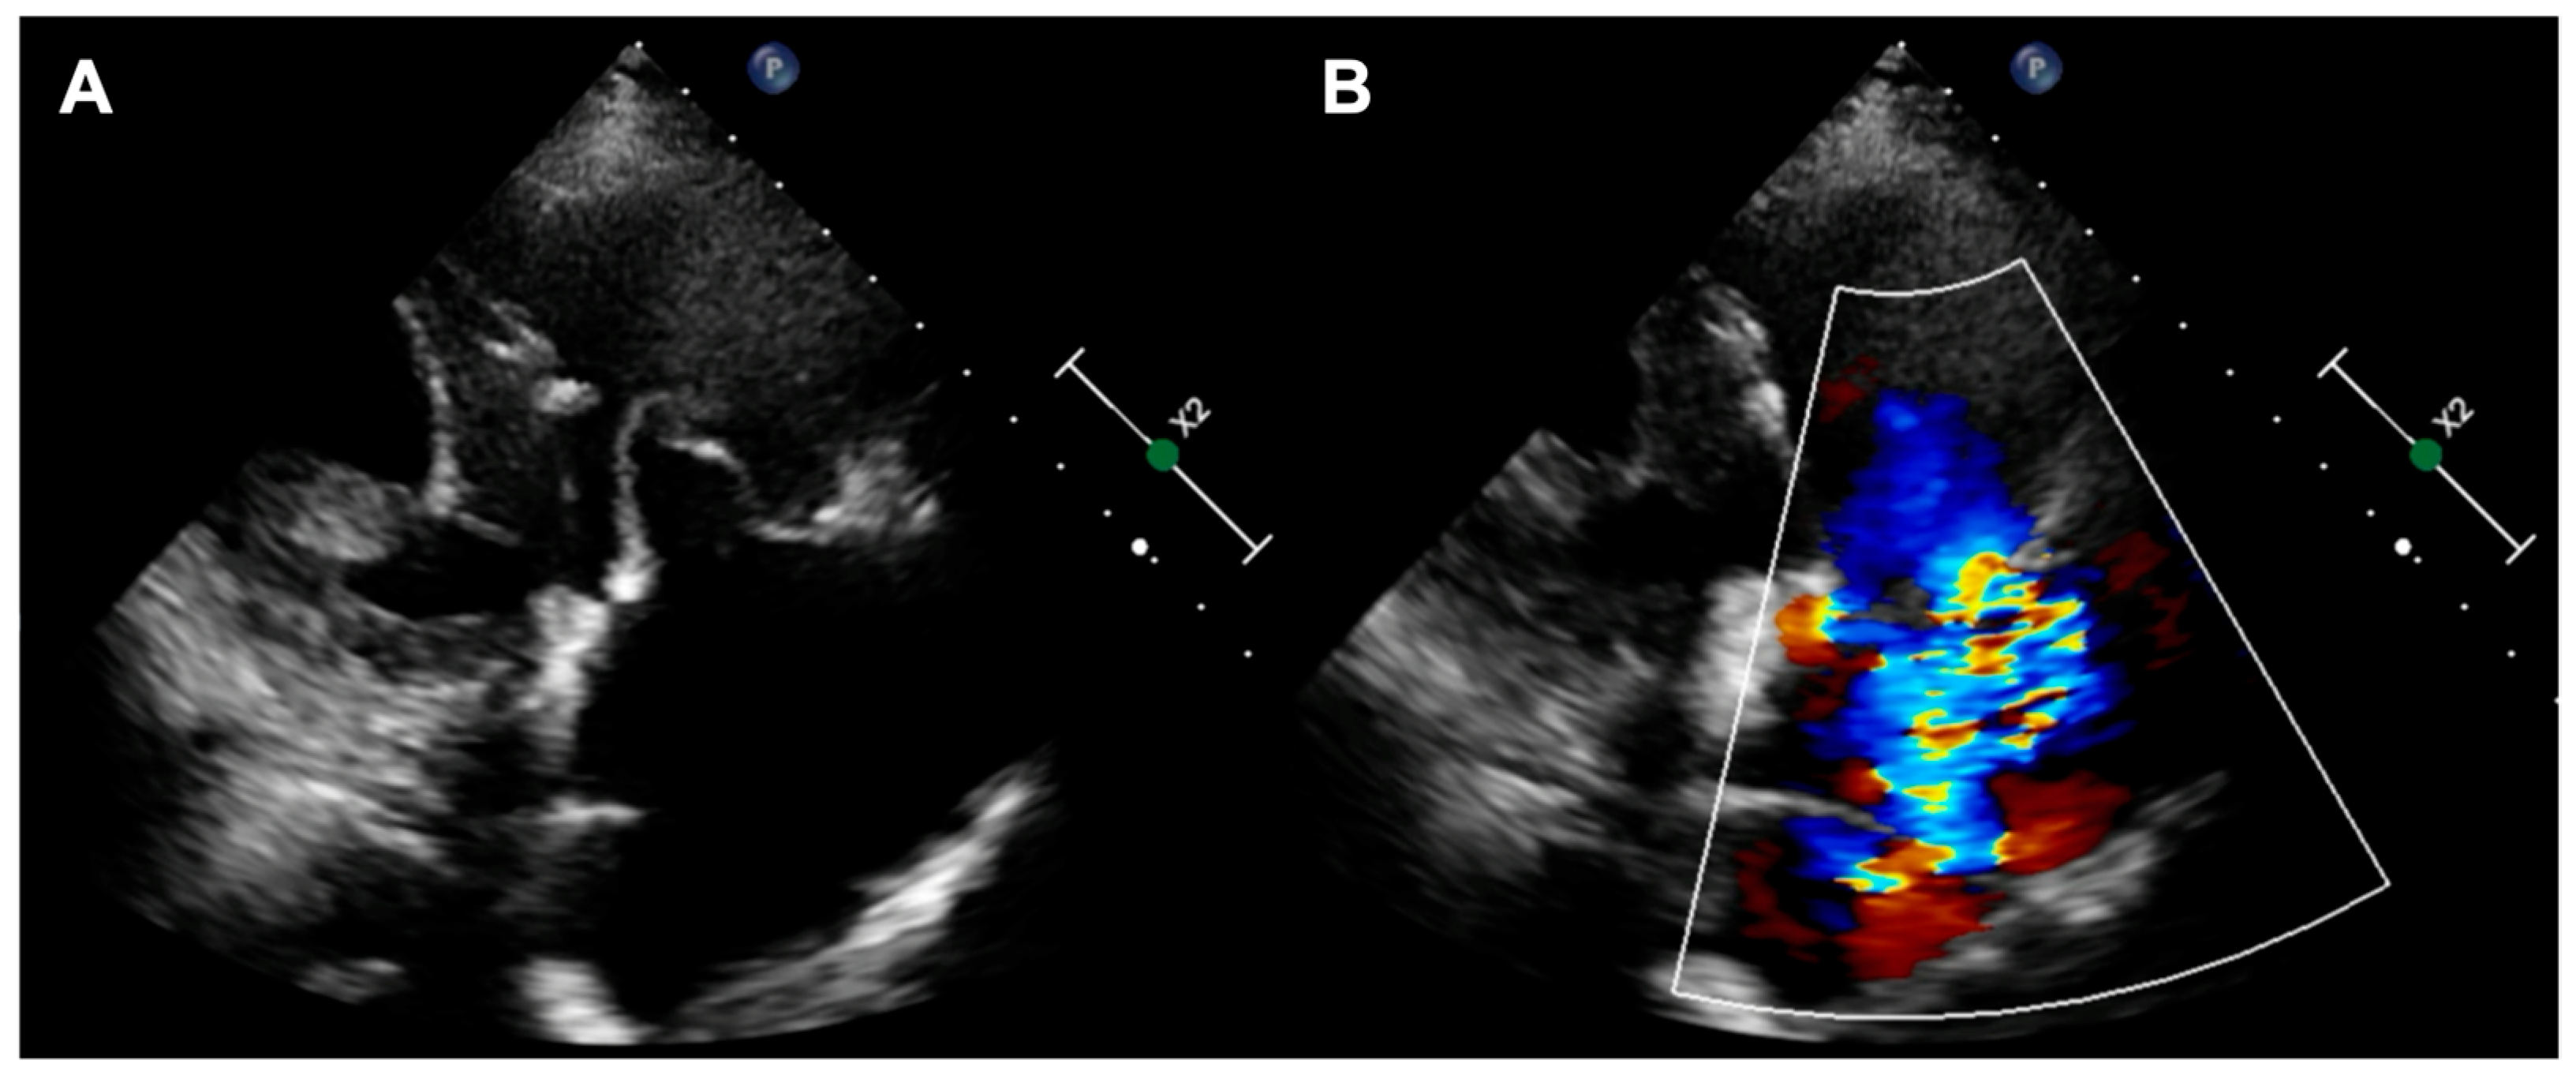

A 73-year-old woman with a history of two surgical interventions—an aortic valve replacement 25 years before and a thoracic aortic aneurysm repair 12 years before—was admitted to the hospital because of persistent heart failure symptoms in functional class NYHA III, accompanied by peripheral edema and ascites. The transthoracic echocardiography showed preserved function of the mechanical aortic prosthesis and torrential TR with tricuspid anulus enlargement. A further transesophageal examination revealed a large, mainly central coaptation deficit between the tricuspid leaflets, located mainly in the central region of the valve (Figure 3). Furthermore, a patent foramen ovale (PFO) with spontaneous right-to-left shunt was also diagnosed. Due to the valve anatomy, the patient was not deemed eligible for the transcatheter edge-to-edge repair. Because of the symptoms’ persistence, a two-step percutaneous procedure was planned. First, the PFO was closed with the 25 mm Amplazer occluder. Two weeks later, the CAVI procedure with the implantation of TricValve system valves (SVC 29 mm; IVC 45 mm) was carried out without complications. (Figure 4) We believed that the PFO closure was necessary before the CAVI procedure because the implantation of venae cavae valves in a patient with a patent PFO would have caused an exacerbation of the right-to-left shunt and possible patient desaturation. In observation, six and twelve months after the procedure, the patient remained on stable doses of oral diuretics and was considered to be in NYHA functional class II, without worsening heart failure or requiring hospitalization.

Figure 3. (A,B) Torrential tricuspid regurgitation in the RV inflow—outflow tract X-plane view; (C) large central coaptation deficit in 3D view. RV—right ventricle.